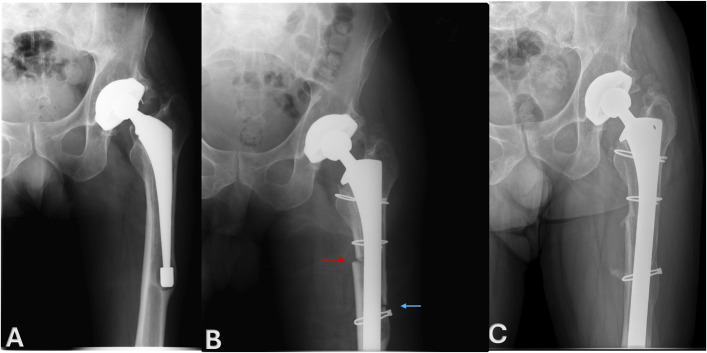

Results: All patients had preoperative varus femoral deformity (mean 16.3° ± 5.7°). The mean postoperative alignment was 4.3 ± 1.6° varus achieving an average correction of 12° (95% CI -15.7 to -8.3, p < 0.0001). Both the ETO and the medial corticotomy consolidated in 10 of 11 patients (91%) with available 1-year radiographs at a mean of 11 ± 7.7 months. The mean HHS improved significantly from 42 preoperatively to 82 at 5-year follow-up (p = 0.0002). Complications related to the ETO and corticotomy occurred in 4 patients (30%), including 1 intraoperative fracture, 1 postoperative greater trochanteric fracture, 1 nonunion of the medial corticotomy, and 1 postoperative wound-hematoma. All femoral components remained well fixed at final follow-up.

Abstract Image